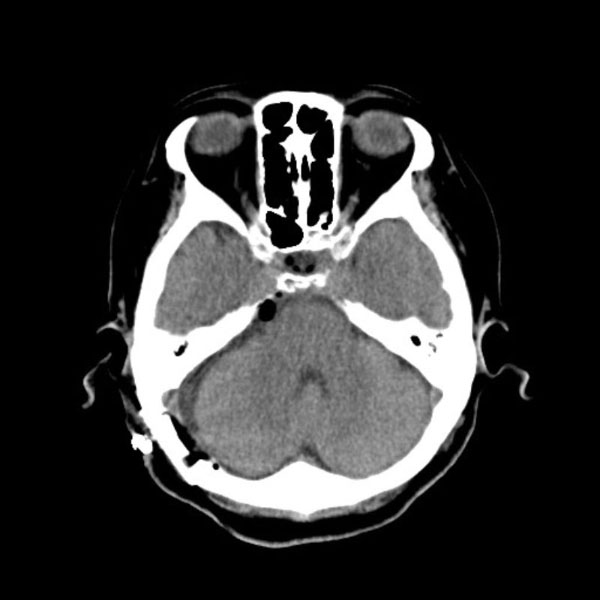

手術後

(CT)